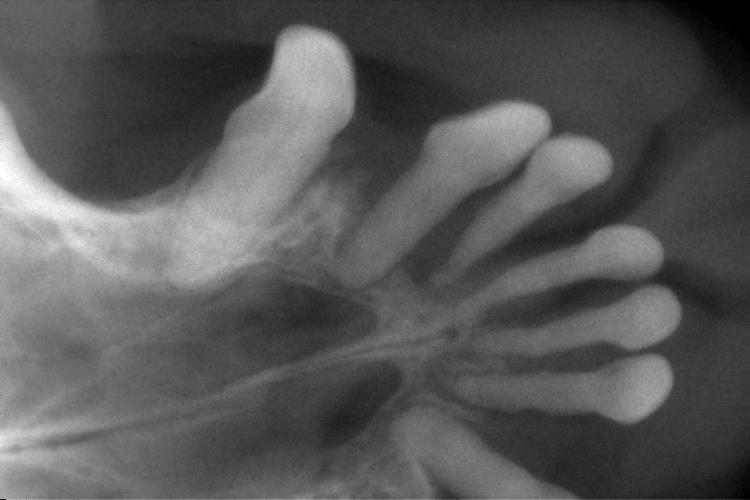

下の写真は下顎切歯のレントゲンです。

〇印は上顎と同じく歯槽骨が溶け、歯がぐらついていました。

また、歯科処置の時点ですでに抜けている歯もありました。